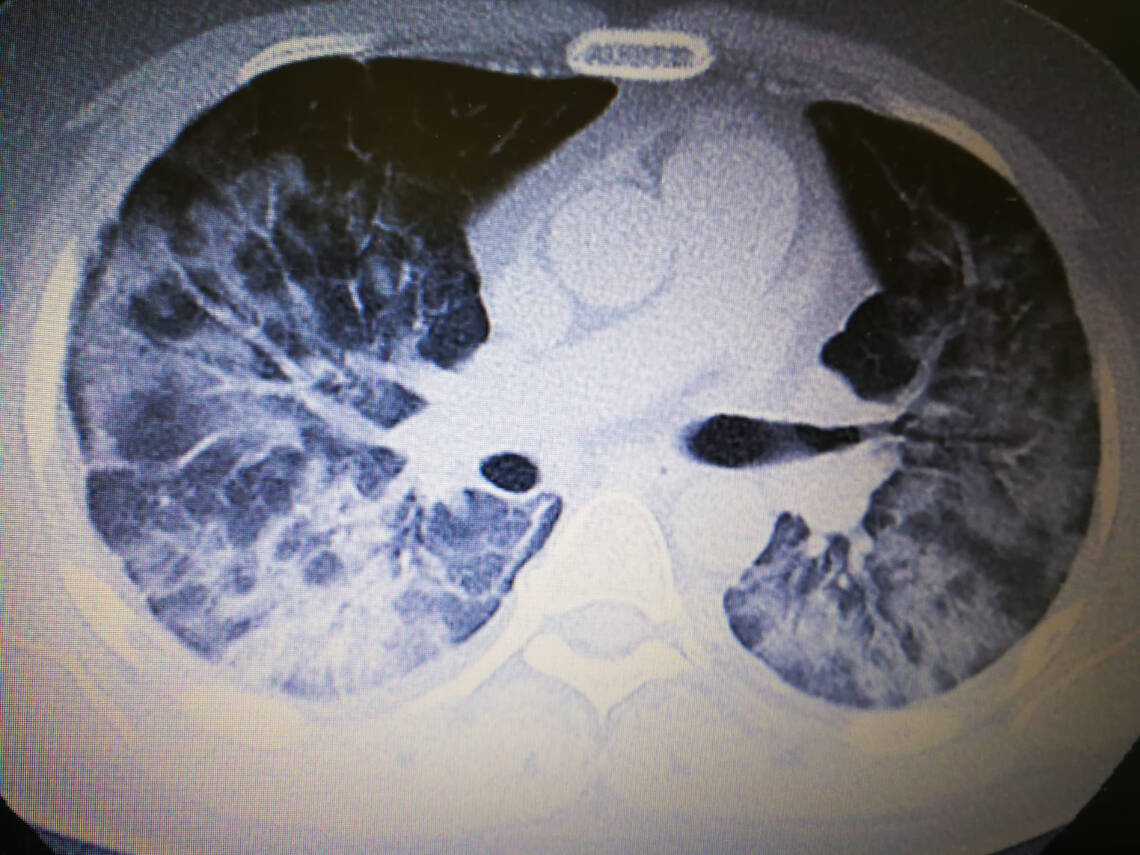

Bildgebende Verfahren. Bettseitige a. p. Röntgen-Thoraxaufnahmen zeigen in 60 % aller COVID-19-Fälle bilaterale Infiltrationen. In CT-Aufnahmen finden sich schon in frühen Krankheitsstadien die für COVID-19 typischen bilateralen subpleuralen Milchglastrübungen und Konsolidierungen von Lungenabschnitten (Abb. 1) [2].

Die Empfehlungen weisen darauf hin, dass CT-Untersuchungen zum Schutz von Personal und Patienten zurückhaltend und nur bei therapeutischen Konsequenzen durchgeführt werden sollten.